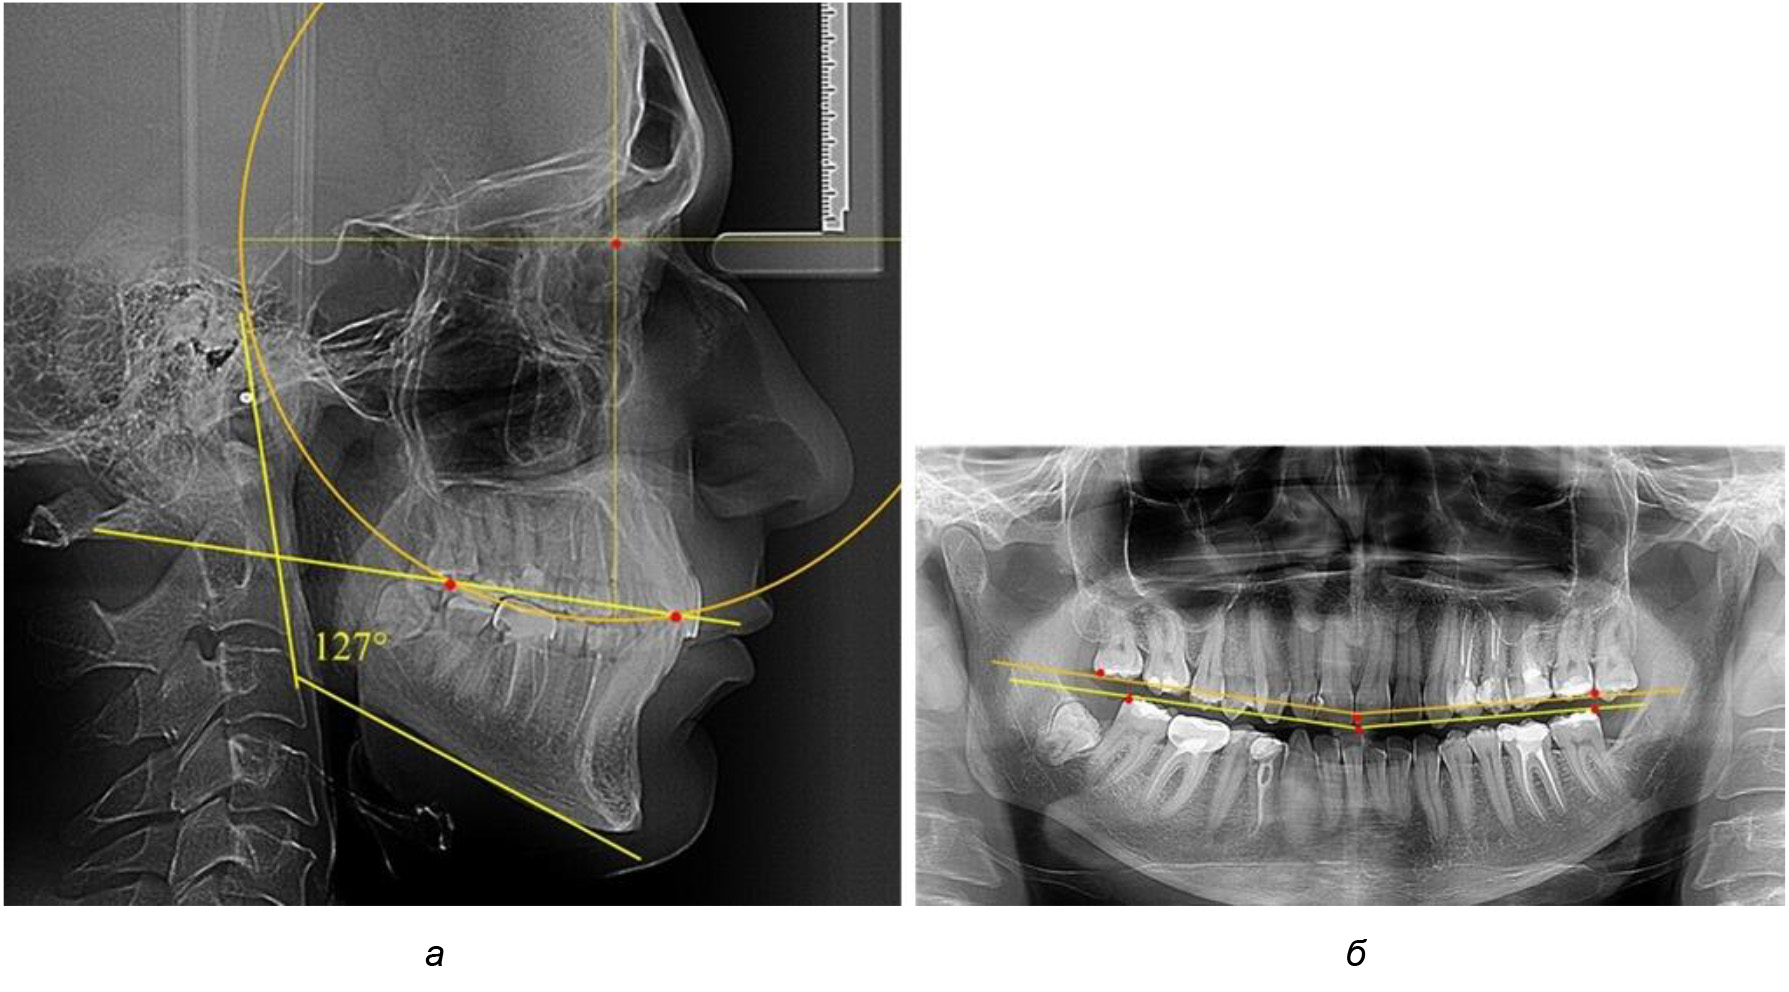

В 3-ю подгруппу вошли ТРГ и ОПТГ 14 человек 1-й группы, что составило (22,58 ± 5,31) % от общего количества людей 1-й группы. Величина угла нижней челюсти в среднем составила (114,85 ± 2,87)° и характеризовала горизонтальный тип нижней челюсти.

Глубина кривой Spee в среднем по 2-й подгруппе составил (2,94 ± 0,47) мм, что было меньше, чем в других подгруппах. Деление величины радиуса круга к длине окклюзионной линии составило 1,616 ± 0,02 (рис. 4).

Рис. 3. Особенности кривой Spee на ТРГ (а) и ОПТГ (б) при нейтральном типе роста нижней челюсти

Рис. 4. Особенности кривой Spee на ТРГ (а) и ОПТГ (б) у людей с горизонтальным типом лица